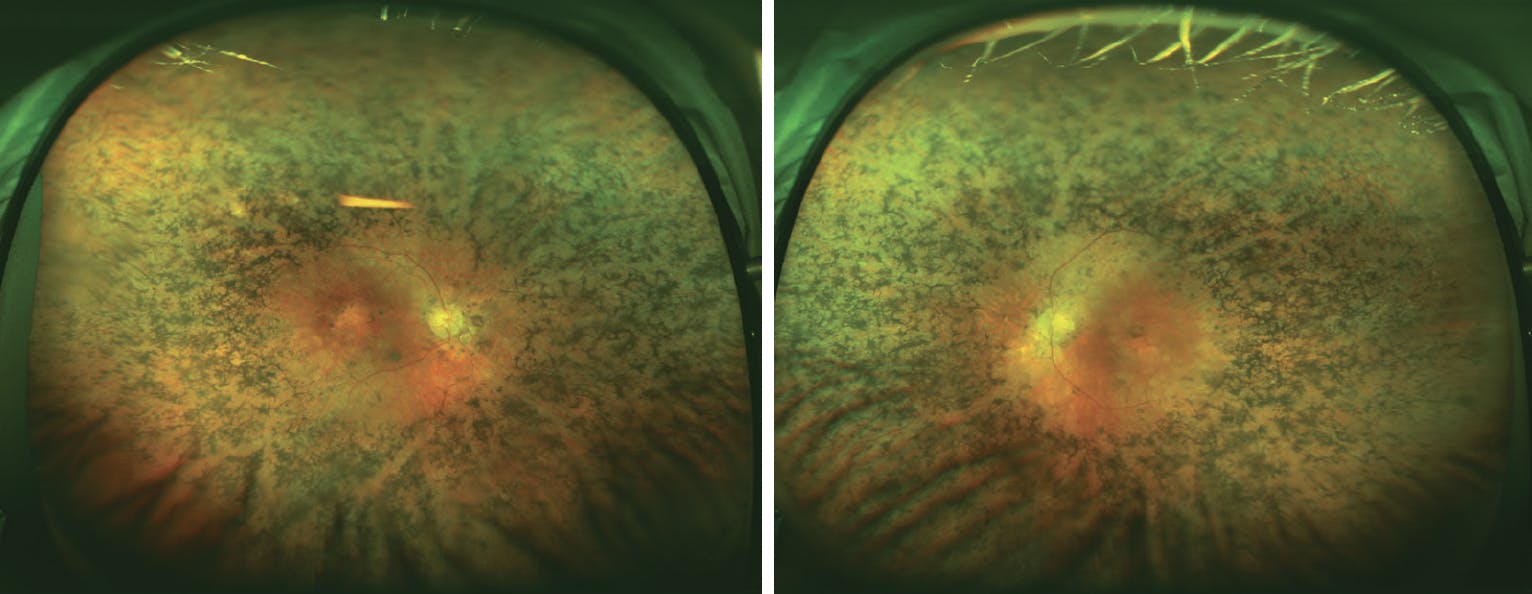

Before proceeding with genetic testing, clinicians must obtain a comprehensive family history, medical history, ocular examination, and directed ocular imaging. A detailed family history (eg, hearing loss, developmental or cognitive delays, polydactyly, etc) can help establish heritability and determine whether the retinal findings are part of a syndromic disease. These findings should be included in the lab request for genetic testing to aid in the interpretation of results (Figure).

<p>Figure. This patient with congenital hearing loss and progressive vision loss had pathogenic variants in the <i>MYO7A</i> gene, consistent with Usher type 1B.</p>

Figure. This patient with congenital hearing loss and progressive vision loss had pathogenic variants in the MYO7A gene, consistent with Usher type 1B.